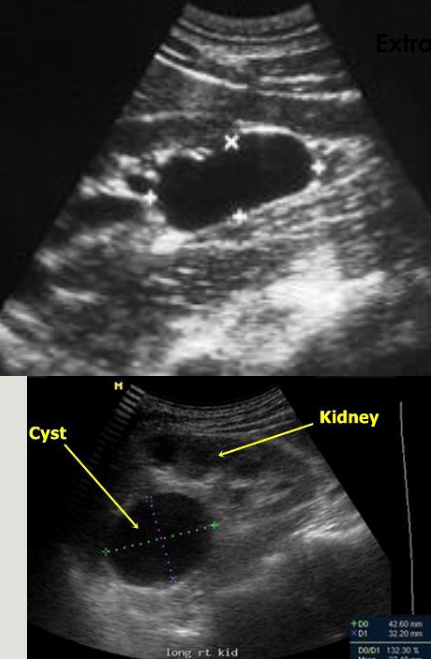

3 types of renal masses

Cystic - anechoic, smooth walls, posterior enhancement

Solid - nongeometric shape with irregular borders, poorly

defined interface, low-level internal echoes

Complex - Shadowing; characteristics of both cystic and

solid components